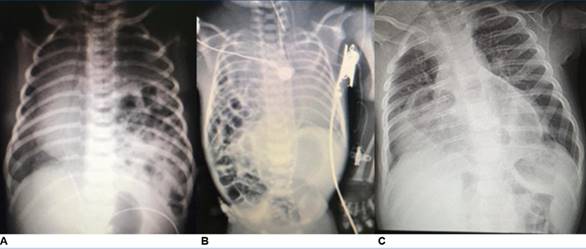

Para la evaluación inicial del paciente, se debe obtener lo antes posible una radiografía de tórax (Figura 1).